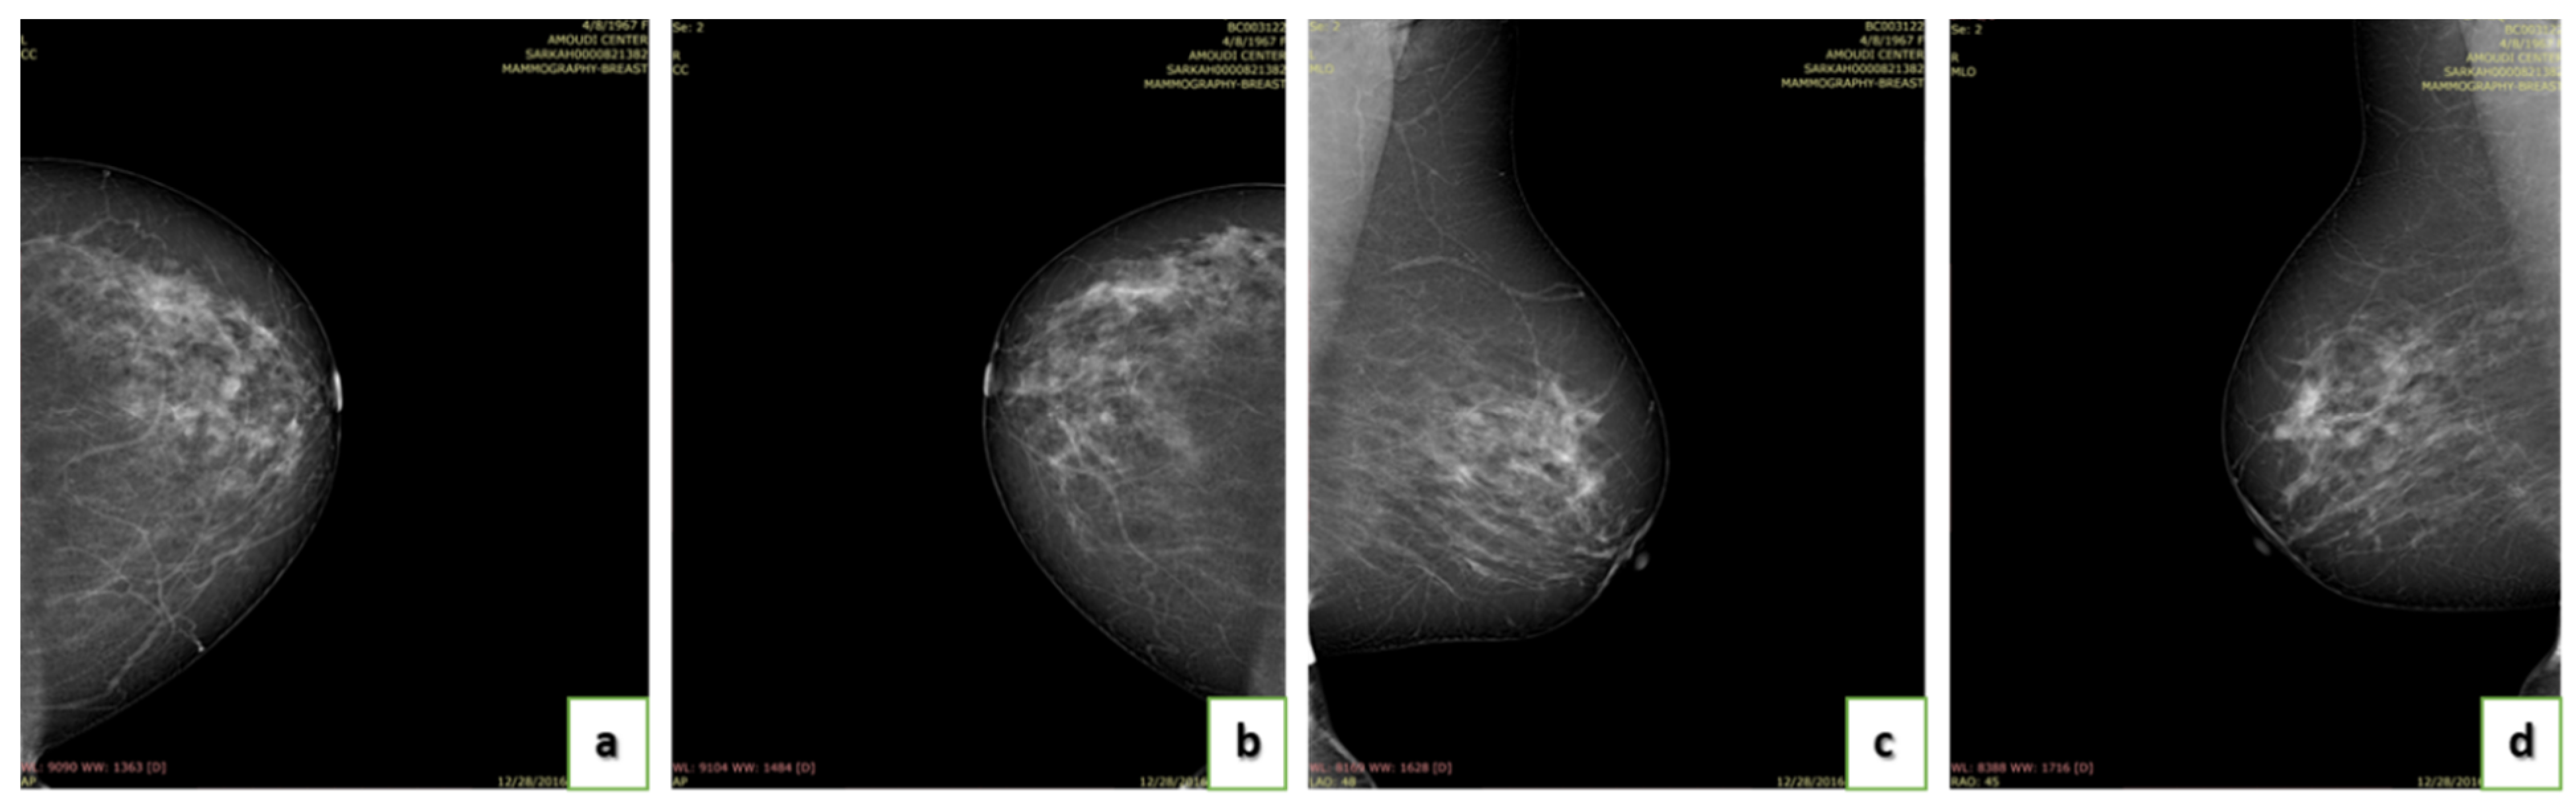

4.4. Breast Density

- A (0–25%): Almost entirely fatty indicates that the breasts are almost entirely composed of fat. One out of ten women has this result.

- B (25–50%): Scattered areas of fibroglandular density indicate some scattered areas of density, but most of the breast tissue is non-dense. Four out of ten women have this result.

- C (50–75%): Heterogeneously dense indicates that there are some areas of non-dense tissue but that most of the breast tissue is dense. Four out of ten women have this result.

- D (75–100%): Extremely dense indicates that nearly all breast tissue is dense. One out of each women has this result.